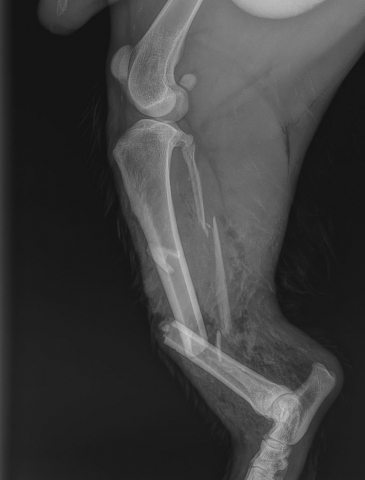

W leczeniu chirurgicznym załamań wykorzystujemy różne implanty, od gwoździ Kirschnera po płyty blokowane.